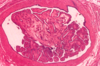

Breast - fibrocystic change with fibrosis and cyst formation

Dense connective tissue with dilated ducts and cyst formation

Blue domed cyst (fibrocystic change)

Blue-domed cyst (fibrocystic change)